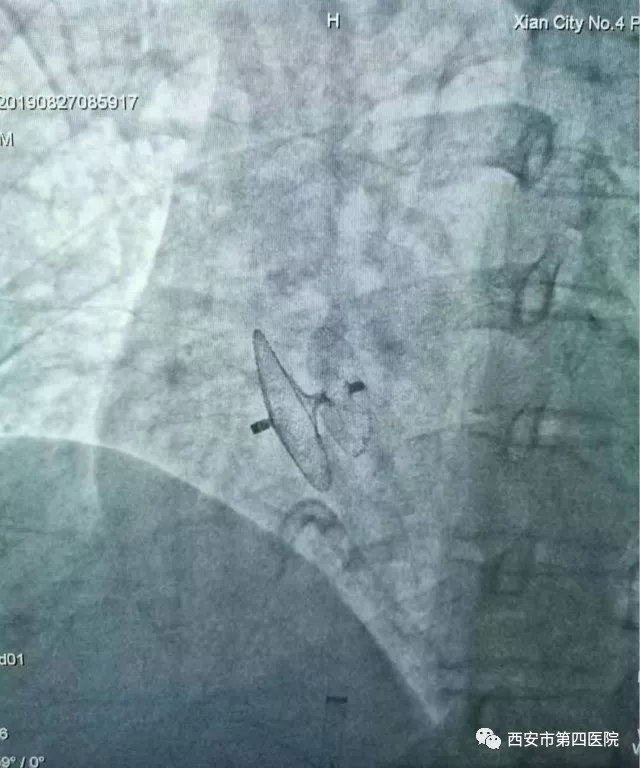

具体手术方式为:患者取平卧位,常规消毒,利多卡因局麻,成功穿刺右侧股静脉后置入鞘管,在超滑导丝引导下经未闭卵圆孔送5F右心导管至左上肺静脉,然后交换加硬导丝至左上肺静脉,沿加硬导丝送输送鞘至左心房,经输送鞘送卵圆孔未闭封堵器PF2535至卵圆孔处,超声下观察封堵期位置合适、无分流,正侧位观察封堵器位置合适,遂释放封堵器,正侧位x线下,超声下提示封堵成功,拔出鞘管,安返病房。

上图为封堵器进入指定位置。

完全打开的封堵器,经超声及X线确认封堵完成,无分流现象,手术成功。